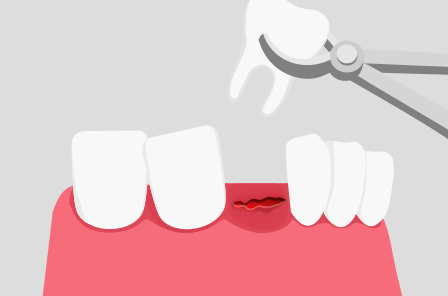

STEP 2

잇몸 절개 및 발치

마취가 잘 되었는지 확인 후에 절개하여 발치를 합니다.

치아 상태에 따라 치료과정은 조금씩 다를 수 있으며, 치아를 쪼개서 꺼내기도 합니다.